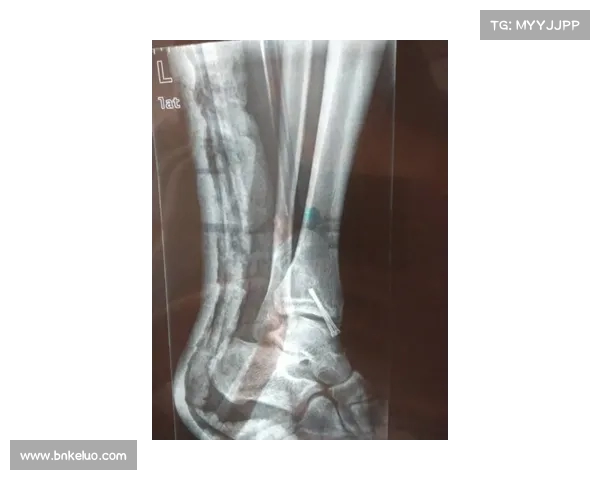

从视频回放来看,穆西亚拉的受伤并不是因为单纯的碰撞,而是由于身体过度扭转后与对方球员发生直接接触,导致腿部剧烈受力。此种情况常见于高速冲刺或突发性变向时,运动员的腿部受到极大冲击而导致骨折或韧带损伤。由于受伤位置较为特殊,穆西亚拉的腓骨骨折需要紧急处理,这也意味着他无法继续完成比赛。

此役过后,穆西亚拉立刻被送往当地医院,接受了详细的影像学检查。初步结果显示,他的腓骨可能存在不同程度的裂痕或骨折,这无疑是一个让人非常担忧的情况。尤其对于一名速度型球员而言,任何涉及下肢骨折的伤情都可能严重影响其未来的竞技状态。

腓骨骨折是运动员常见的骨骼伤害之一,尽管腓骨在解剖结构上不像股骨、髋骨那样承担主要承重功能,但它却在运动员的行动灵活性中起到了至关重要的作用。腓骨主要负责支撑小腿的肌肉力量,并帮助控制运动中的平衡。对于穆西亚拉这样的攻击型球员来说,腓骨骨折可能对他快速变向、突破等动作造成巨大影响。

根据医学专家的分析,腓骨骨折的严重性不仅取决于骨折的具体位置,还取决于骨折的程度。如果骨折只是在腓骨的非承重部位,恢复的难度相对较低,运动员可能在几个月内恢复正常训练。然而,如果骨折发生在承重部位,或者伴随其他软组织损伤,如韧带撕裂、关节脱位等,那么恢复时间可能会大大延长,甚至影响球员的职业生涯。

在穆西亚拉的案例中,尽管初步检查表明他的骨折部位较为靠近小腿的上部,但是否伴随其他损伤仍需进一步评估。这一系列因素直接决定了他的康复周期,是否能按时恢复并回到赛场上,也将影响拜仁慕尼黑和德国队的阵容调整。